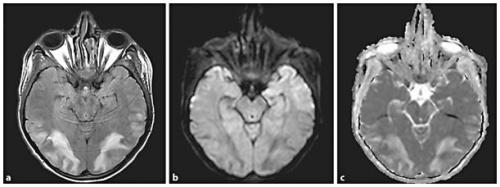

רזולוציה (Resolution) מלאה של ממצאי ההדמיה נחשבת כמעט כהגדרה של התסמונת על אף שלא ברור התזמון המיטבי לביצוע הדמיית ביקורת (תמונה 2), אך היא מתרחשת כנראה בין פרק זמן של ימים בודדים עד שבועות [11], [2]. על אף התמונה המתוארת כאופיינית, קיימים מקרים רבים בהם ההדמיה אינה תואמת את תיאור זה. תוארו מקרים עם מעורבות קדמית משמעותית. יש גם מקרים מתועדים של מעורבות קורטיקאלית (Cortical), נזקים בלתי הפיכים נקודתיים, דימומים לתוך נגעים ומעורבות חד צדדית (תמונה 3).

במקרים אחרים נצפית מעורבות של גזע המוח וכן של גרעיני הבסיס. במקרים בהם מעורבות זו משמעותית, תתכן התפתחות Hydrocephalus ולחץ על גזע המוח[11] , [2] , [12].